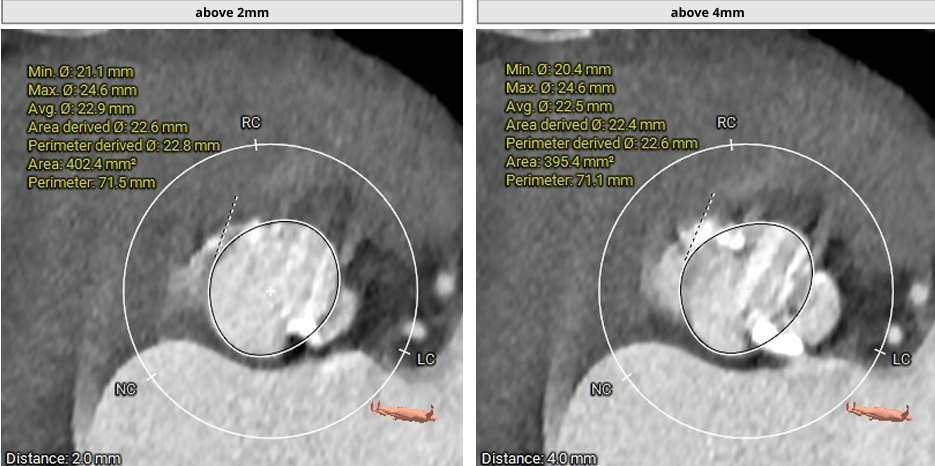

主动脉根部CT测量数据

瓣上结构评估

1. TYPE0型二叶瓣,根据主动脉根部CT评估情况,决定预选22mm球囊预扩,植入VenusAL26瓣膜。